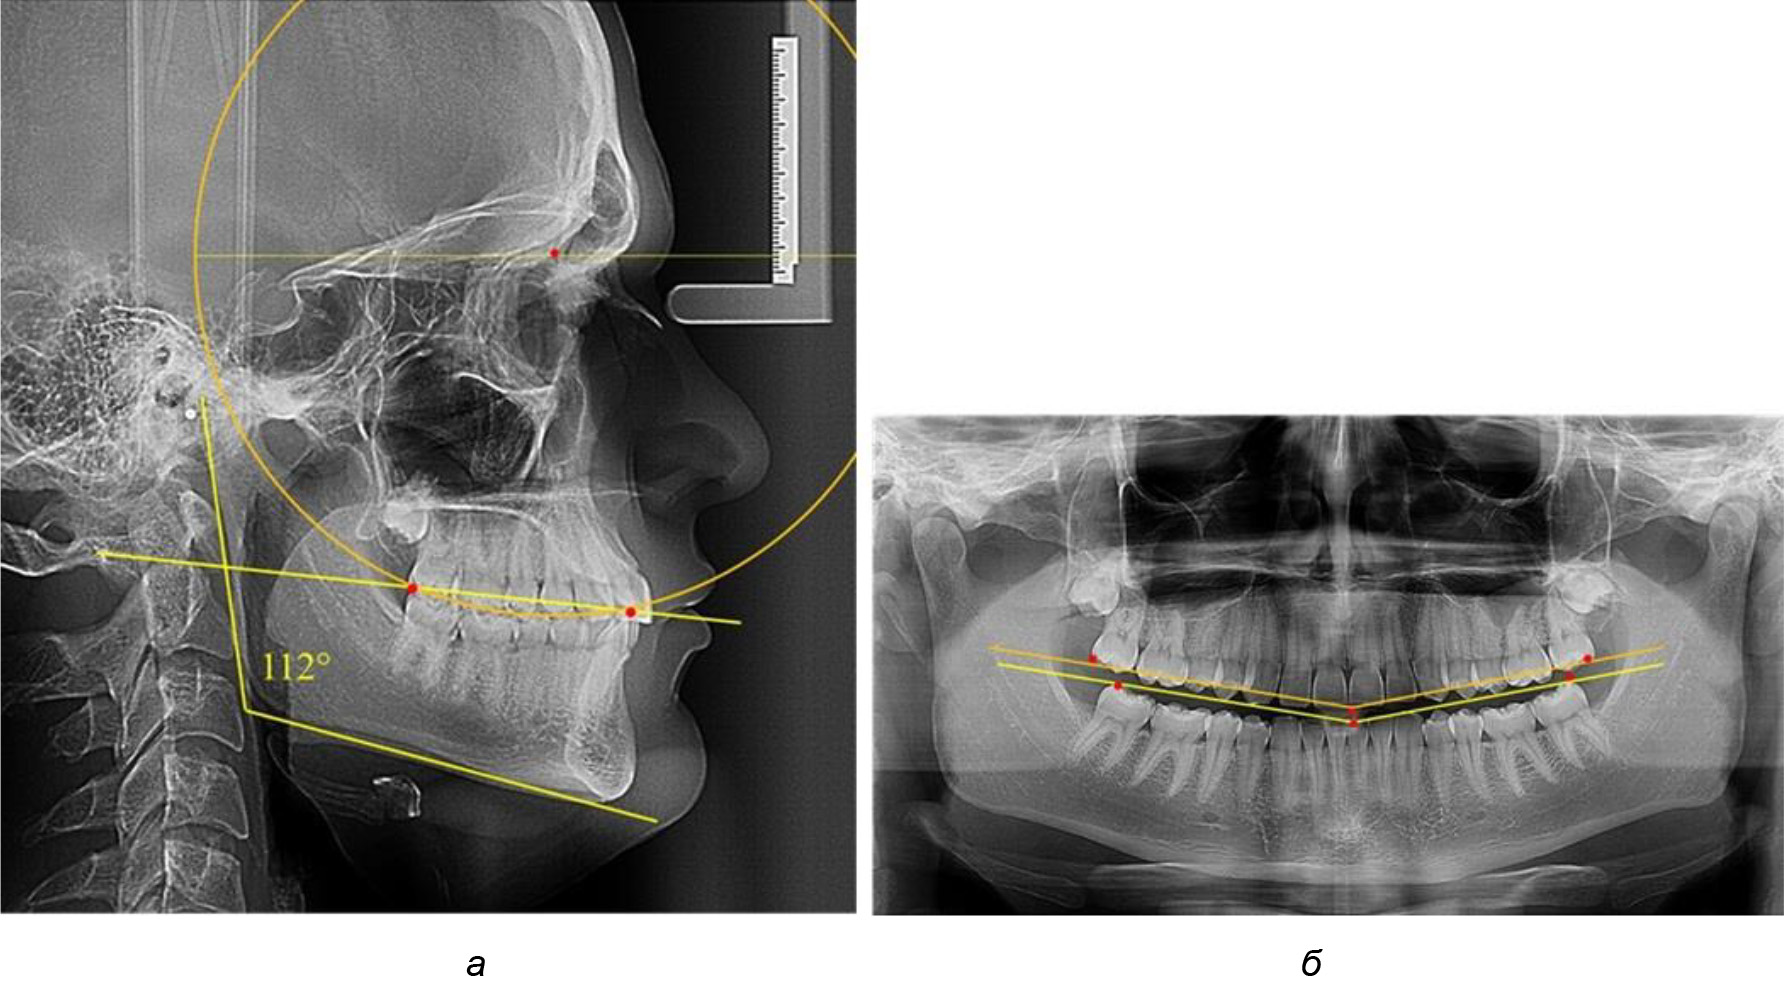

Глубина кривой Spee в среднем по 2-й подгруппе составила (5,69 ± 1,57) мм, что было достоверно больше, чем у людей с физиологической окклюзией (р ˂ 0,05). Достоверных различий с показателями, полученными при анализе ТРГ и ОПТГ, нами не отмечено (р ˃ 0,05). Отношение радиуса окружности к сагиттальному размеру окклюзионной линии в среднем по подгруппе составляло 1,372 ± 0,042 и не соответствовало числу Фибоначчи, что может быть использовано в качестве диагностического критерия определения патологической формы кривой Spee. После лечения пациентов техникой «прямой» дуги было отмечено незначительное увеличение сагиттального размера окклюзионной лини в среднем на (2,12 ± 0,77) мм. Однако окклюзионная линия практически касалась окклюзионного контура всех жевательных зубов, и отмечалось практически полное отсутствие кривой Spee.

Таким образом, проведенное лечение техникой «прямой» дуги способствует нормализации окклюзионного равновесия и торку передних зубов, однако не соответствует оптимальному окклюзионному статусу, характеризующему физиологическую окклюзию. При этом величина нижнечелюстного угла оставалась на прежнем уровне (рис. 5).

Рис. 5. Особенности ТРГ при патологической кривой Spee до лечения (а) и после лечения (б) техникой «прямой» дуги

После лечения пациентов техникой «прямой» дуги, так же как и в 1-й подгруппе, было отмечено увеличение сагиттального размера окклюзионной лини в среднем на (2,38 ± 0,83) мм. Окклюзионная линия практически касалась окклюзионного контура всех жевательных зубов, и отмечалось практически полное отсутствие кривой Spee, так же как и у людей 1-й подгруппы 2-й группы (рис. 6).

Рис. 6. Особенности ТРГ при оптимальной кривой Spee до лечения (а) и после лечения (б) техникой «прямой» дуги

Таким образом, проведенное лечение техникой «прямой» дуги способствует нормализации окклюзионного равновесия и торку передних зубов, однако не соответствует оптимальному окклюзионному статусу, характеризующему физиологическую окклюзию. При этом величина нижнечелюстного угла оставалась на прежнем уровне.